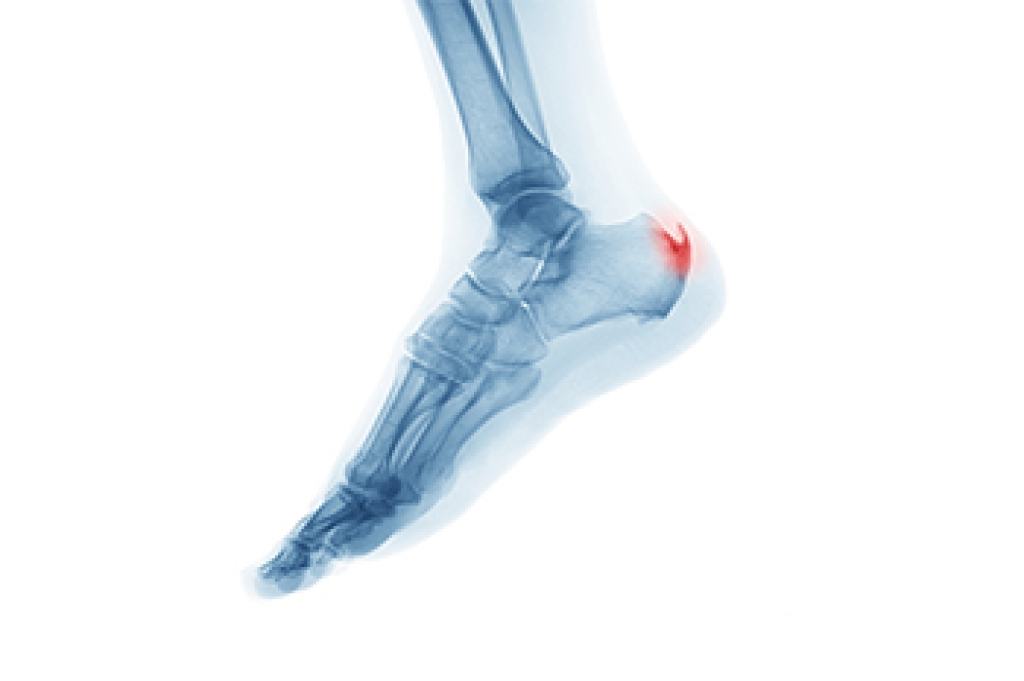

Heel spurs are bony growths that develop on the heel due to stress and inflammation in surrounding tissues. They are commonly seen in two forms. Heel spur syndrome affects the bottom of the heel, and insertional Achilles tendinitis affects the back of the heel where the tendon attaches. Risk factors include flat feet, high arches, excess weight, tight calf muscles, and repetitive impact activities. Symptoms may involve sharp heel pain, stiffness, and discomfort during the first steps of the day. A podiatrist can diagnose the condition, offer custom treatments, and provide guidance to relieve pain and improve function. If heel pain is limiting your daily life, it is suggested that you consult a podiatrist who can offer effective relief and treatment solutions.

Heel spurs are formed by calcium deposits on the back of the foot where the heel is. This can also be caused by small fragments of bone breaking off one section of the foot, attaching onto the back of the foot. Heel spurs can also be bone growth on the back of the foot and may grow in the direction of the arch of the foot.